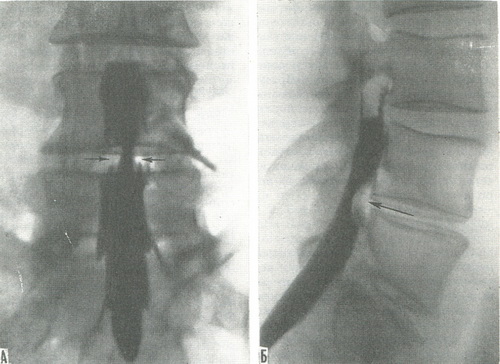

512. Мієлограми.

А - задній знімок; Б - боковий знімок. Стрілками показано розташування хрящової грижі міжхребцевого диска (по Л. Д. Линденбратену).

Мієлографія - вивчення субарахноїдального простору спинного мозку - проводиться за допомогою высокоорганических контрастних речовин або повітря. На задніх і бічних знімках виявляється розподіл контрастної речовини в субарахноїдальному просторі. У цьому випадку за його рельєфу можна судити про поверхні спинного мозку і хребетного каналу (рис. 512). При пухлинах, сращениях, пошкодження диска і хребців змінюється рельєф стінок субарахноїдального простору.